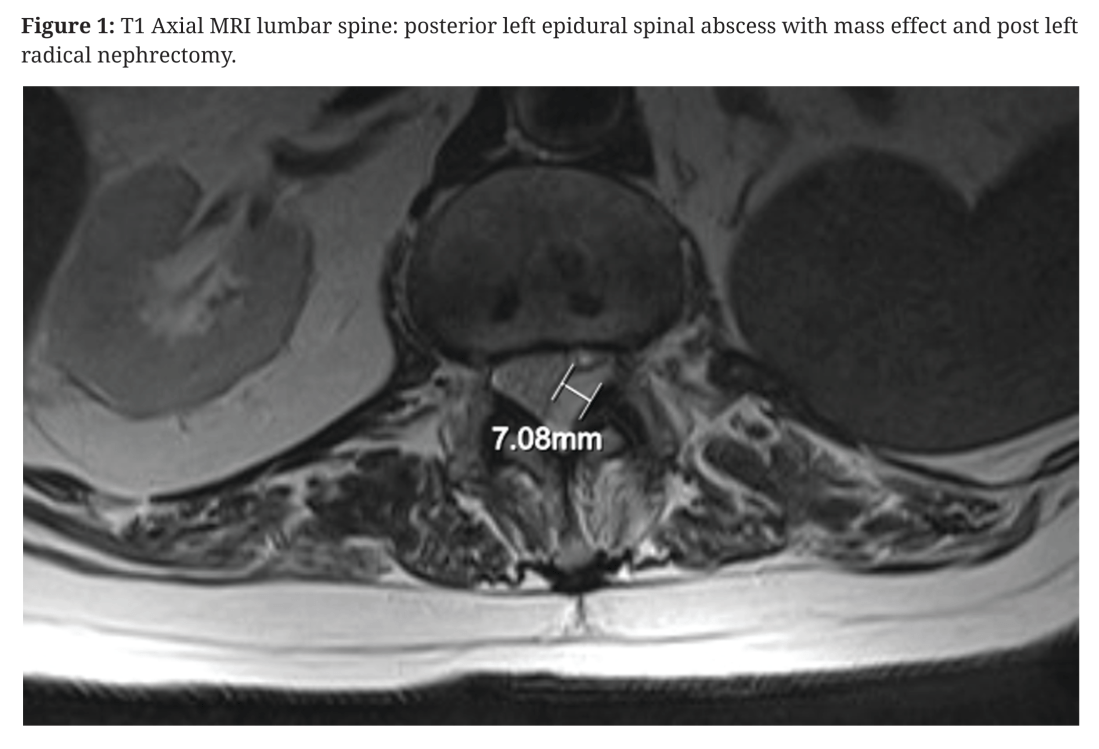

Spinal epidural abscesses

Inspired by Shew et al 2019.[1] Shew et al 2019.[1] This is the first reported case of a spinal epidural abscess as a possible complication of acupuncture treatment in New Zealand. It is the 15th such report I can find in the literature (on PubMed), but this report and most others cannot make irrefutable causal … Continue reading Spinal epidural abscesses